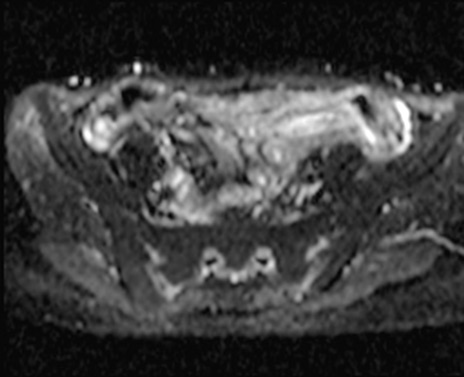

MRI(4日後)